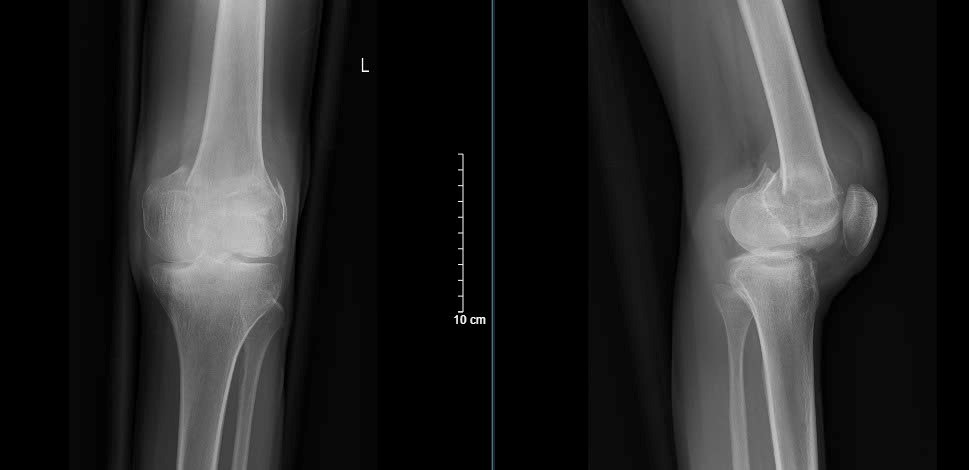

Hình ảnh Xquang trước phẫu thuật